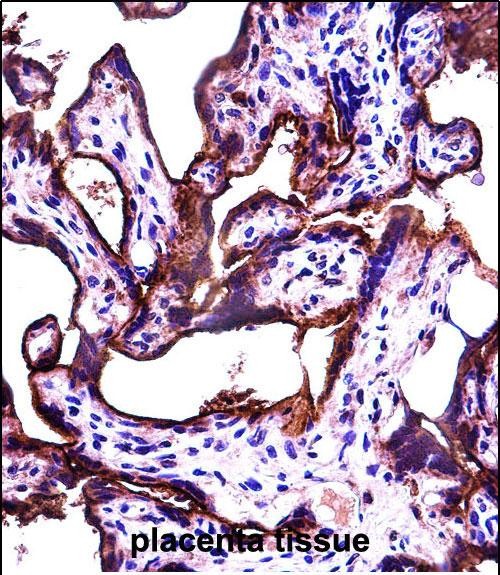

| IHC | 1/100-1/500 | Human,Mouse,Rat |

| Immunogen | This ALPPL2 antibody is generated from rabbits immunized with a KLH conjugated synthetic peptide between 58-86 amino acids from the N-terminal region of human ALPPL2. |

The ALPPL2 (N-term) antibody is designed to target the N-terminal region of the Alkaline Phosphatase, Placental-Like 2 (ALPPL2) protein, also known as germ cell alkaline phosphatase (GCAP). ALPPL2 is a member of the alkaline phosphatase family, which catalyzes the hydrolysis of phosphate esters and plays roles in diverse biological processes, including mineralization, metabolism, and cell signaling. Unlike the placental alkaline phosphatase (ALPP), ALPPL2 is primarily expressed in germ cells and certain cancers, making it a potential biomarker for malignancies such as testicular germ cell tumors, ovarian cancer, and thymic epithelial tumors.

Structurally, ALPPL2 is a glycosylphosphatidylinositol (GPI)-anchored cell surface protein. Its N-terminal domain contributes to enzymatic activity and substrate binding. The ALPPL2 (N-term) antibody is commonly used in research to detect and study the expression, localization, and function of ALPPL2 in normal and pathological tissues. Its specificity for the N-terminal region ensures recognition of the full-length protein, aiding in distinguishing ALPPL2 from other alkaline phosphatase isoforms.

Studies suggest that ALPPL2 overexpression in cancers correlates with tumor progression and metastasis, potentially serving as a therapeutic target. This antibody is utilized in techniques like immunohistochemistry, Western blotting, and flow cytometry to explore ALPPL2's role in oncogenesis and its utility in diagnostic or prognostic applications.